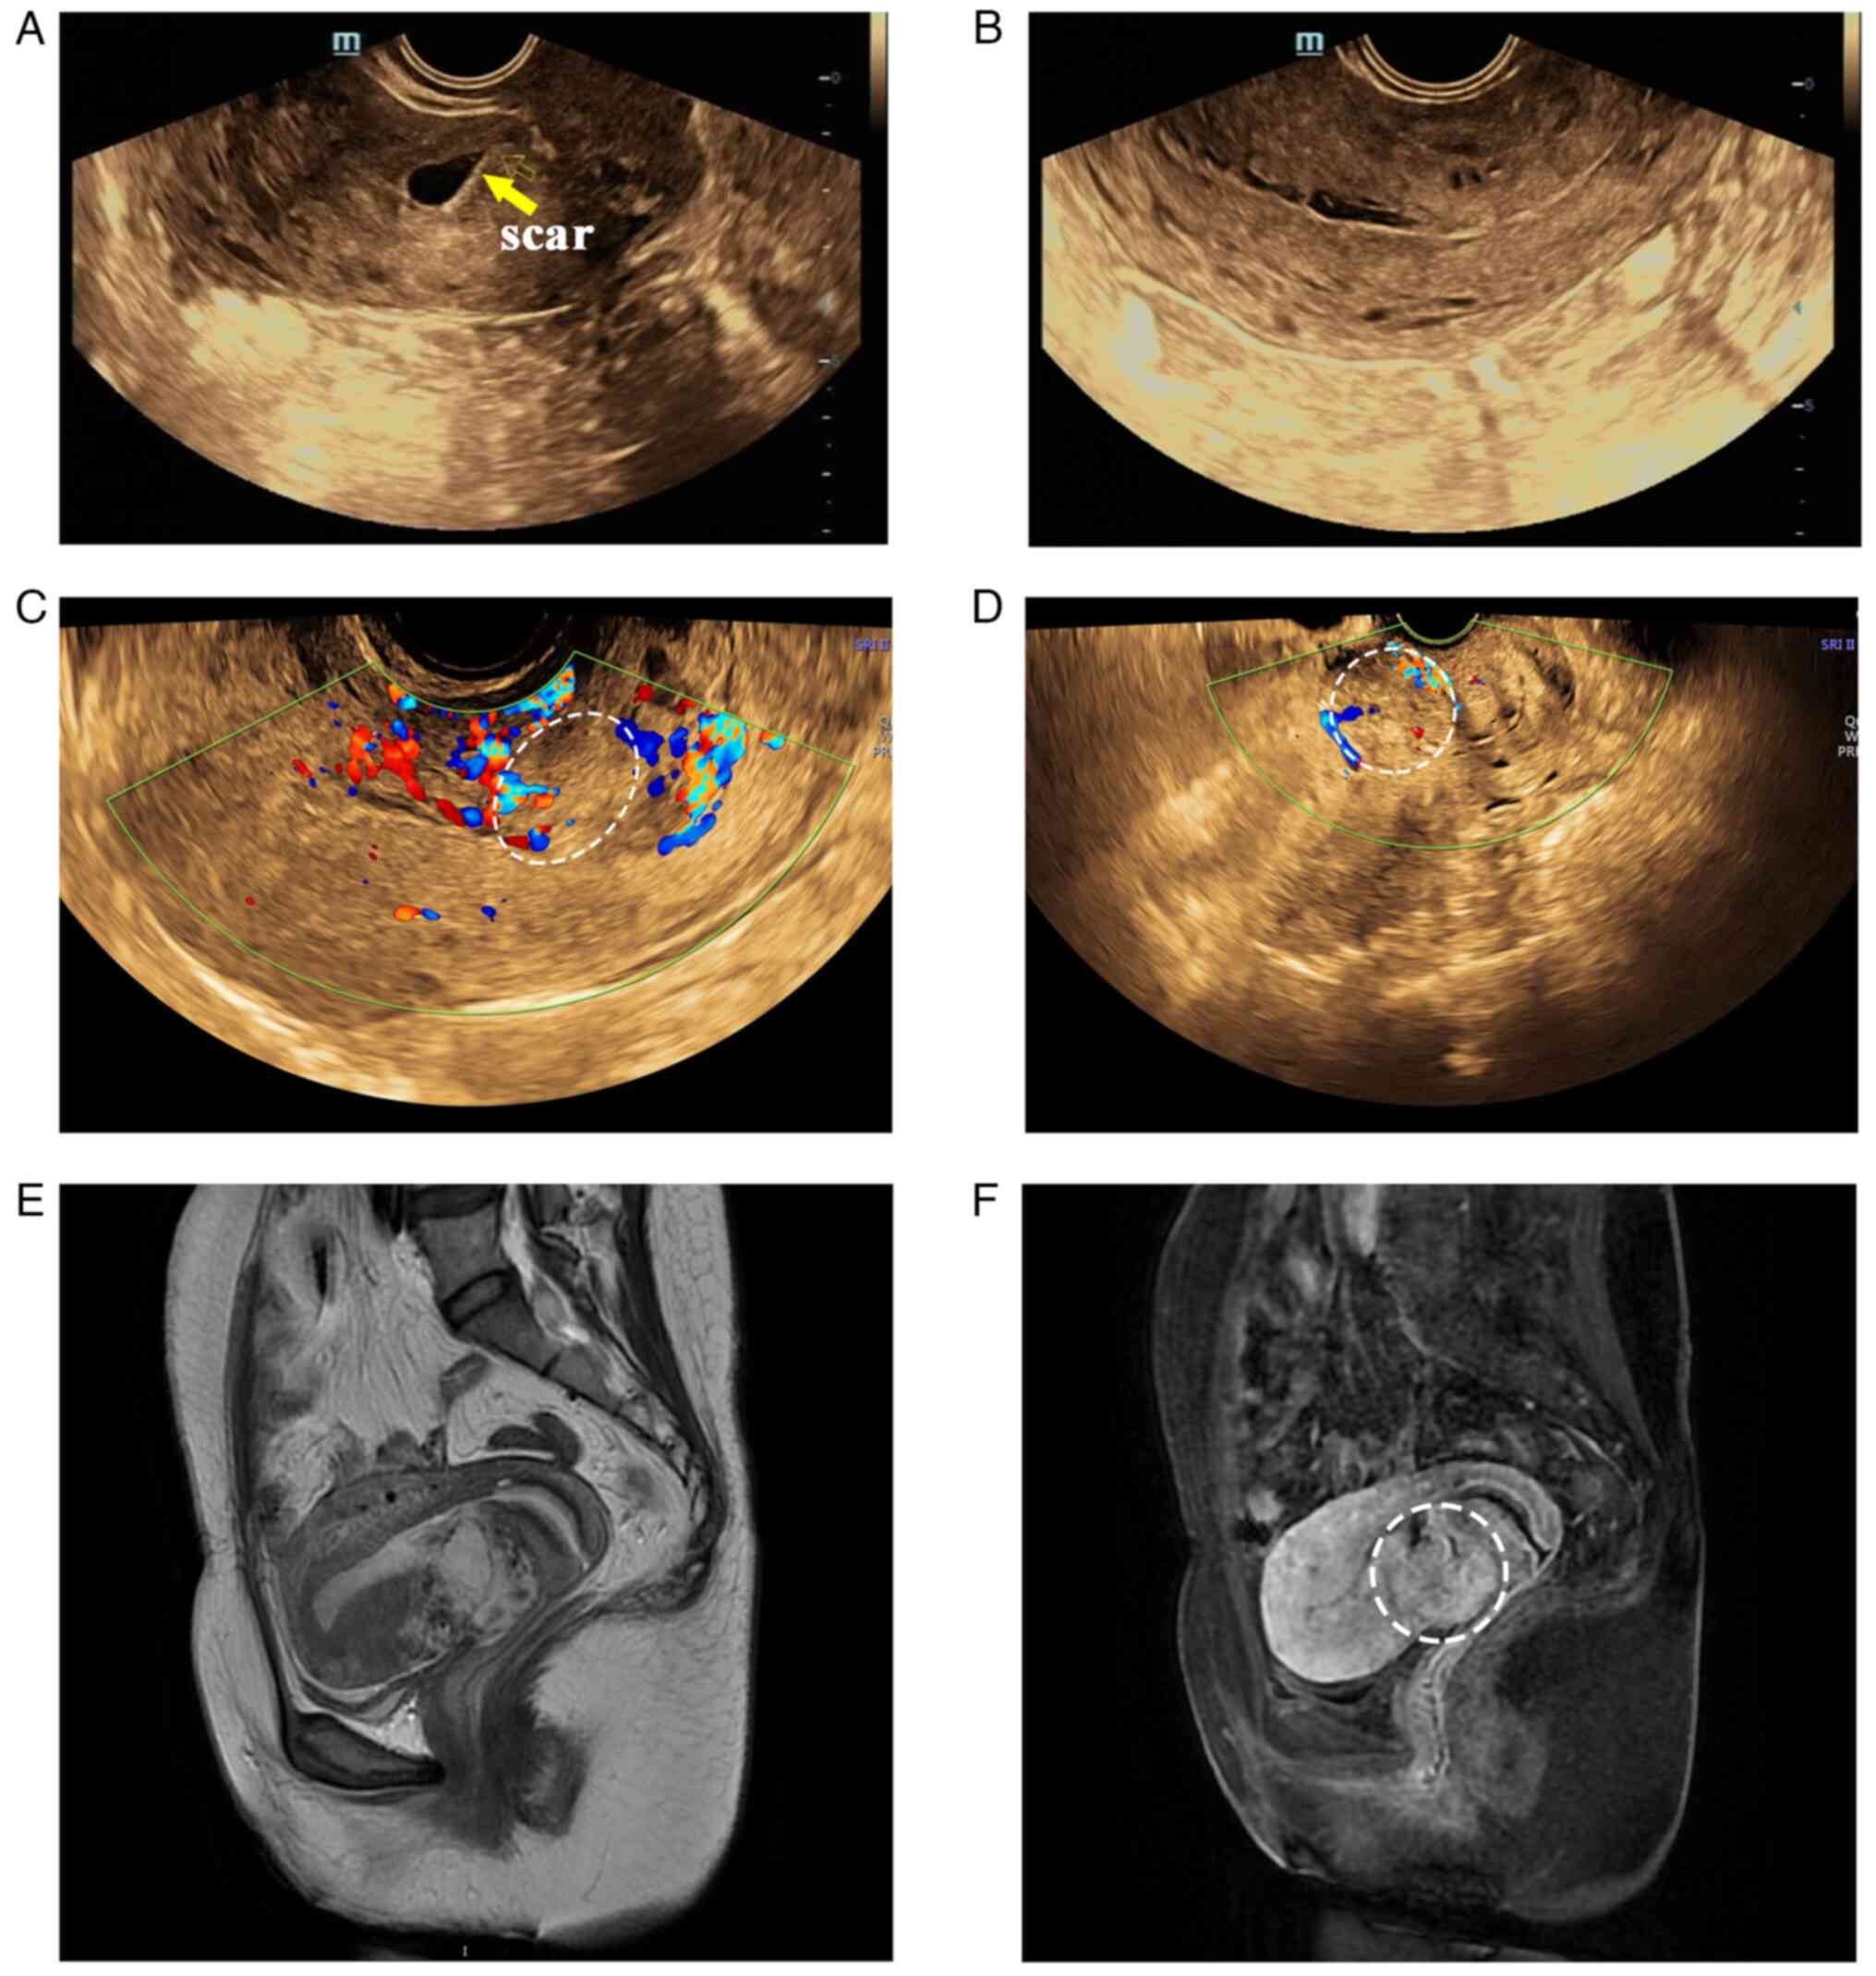

The present study reports a rare case of an exaggerated placental site (EPS) in a caesarean scar that was misdiagnosed as gestational trophoblastic neoplasia (GTN) by imaging, resulting in unnecessary surgical treatment. A 38‑year‑old woman underwent hysteroscopic resection of a cesarean scar pregnancy (CSP). The patient's serum β‑human chorionic gonadotropin (β‑hCG) level was elevated (76,196 mIU/ml) at the 24‑day postoperative follow‑up visit. On postoperative day 51, the patient experienced vaginal bleeding for three days and β‑hCG levels were 2,799 mIU/ml. Ultrasonography and MRI revealed a heterogeneous mass and hypervascularity. The patient was diagnosed with a GTN in a cesarean scar and treated with methotrexate (MTX). β‑hCG levels decreased after 3 MTX doses, but the mass did not change in size and was still hypervascular on imaging. Total hysterectomy was performed due to the serious side effects of chemotherapy and the lack of desire to preserve fertility. The histological findings supported the diagnosis of an EPS reaction. The present case is unique because of the rare intrauterine mass and possibility of retained trophoblastic changes causing EPS. EPS differs from GTN both clinically and pathologically and should be considered a possible diagnosis in any woman who has irregular bleeding following CSP resection.

Figure 1